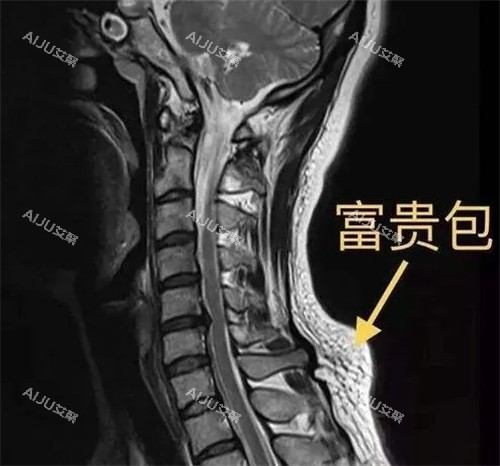

术前检查:MRI核磁共振(价值800元,确认纤维与肌肉粘连程度)